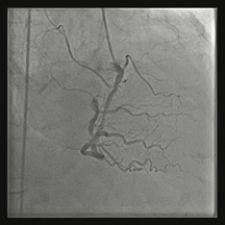

ContextVision’s GOPView iRVPlus uses a continuous adaptive filtration method to analyze every pixel in an image, which guarantees that every structure in the image receives the same level of analysis. This rotationally invariant process ensures that all objects, independent of position and orientation, receive the highest level of image enhancement possible. This eliminates the risk of critical information being overlooked, leading to higher clinical value.

Like all ContextVision products, iRVPlus relies on a proprietary algorithm, GOP, which simultaneously enhances all structures and reduces noise. This anisotropic filtration method enhances image quality of all textures so that more details can be seen while introducing less blur. Additionally, an extensive and growing library of adaptive filters fine-tunes images. This level of image enhancement can enable a dose reduction of more than one-third without any compromise of image quality.